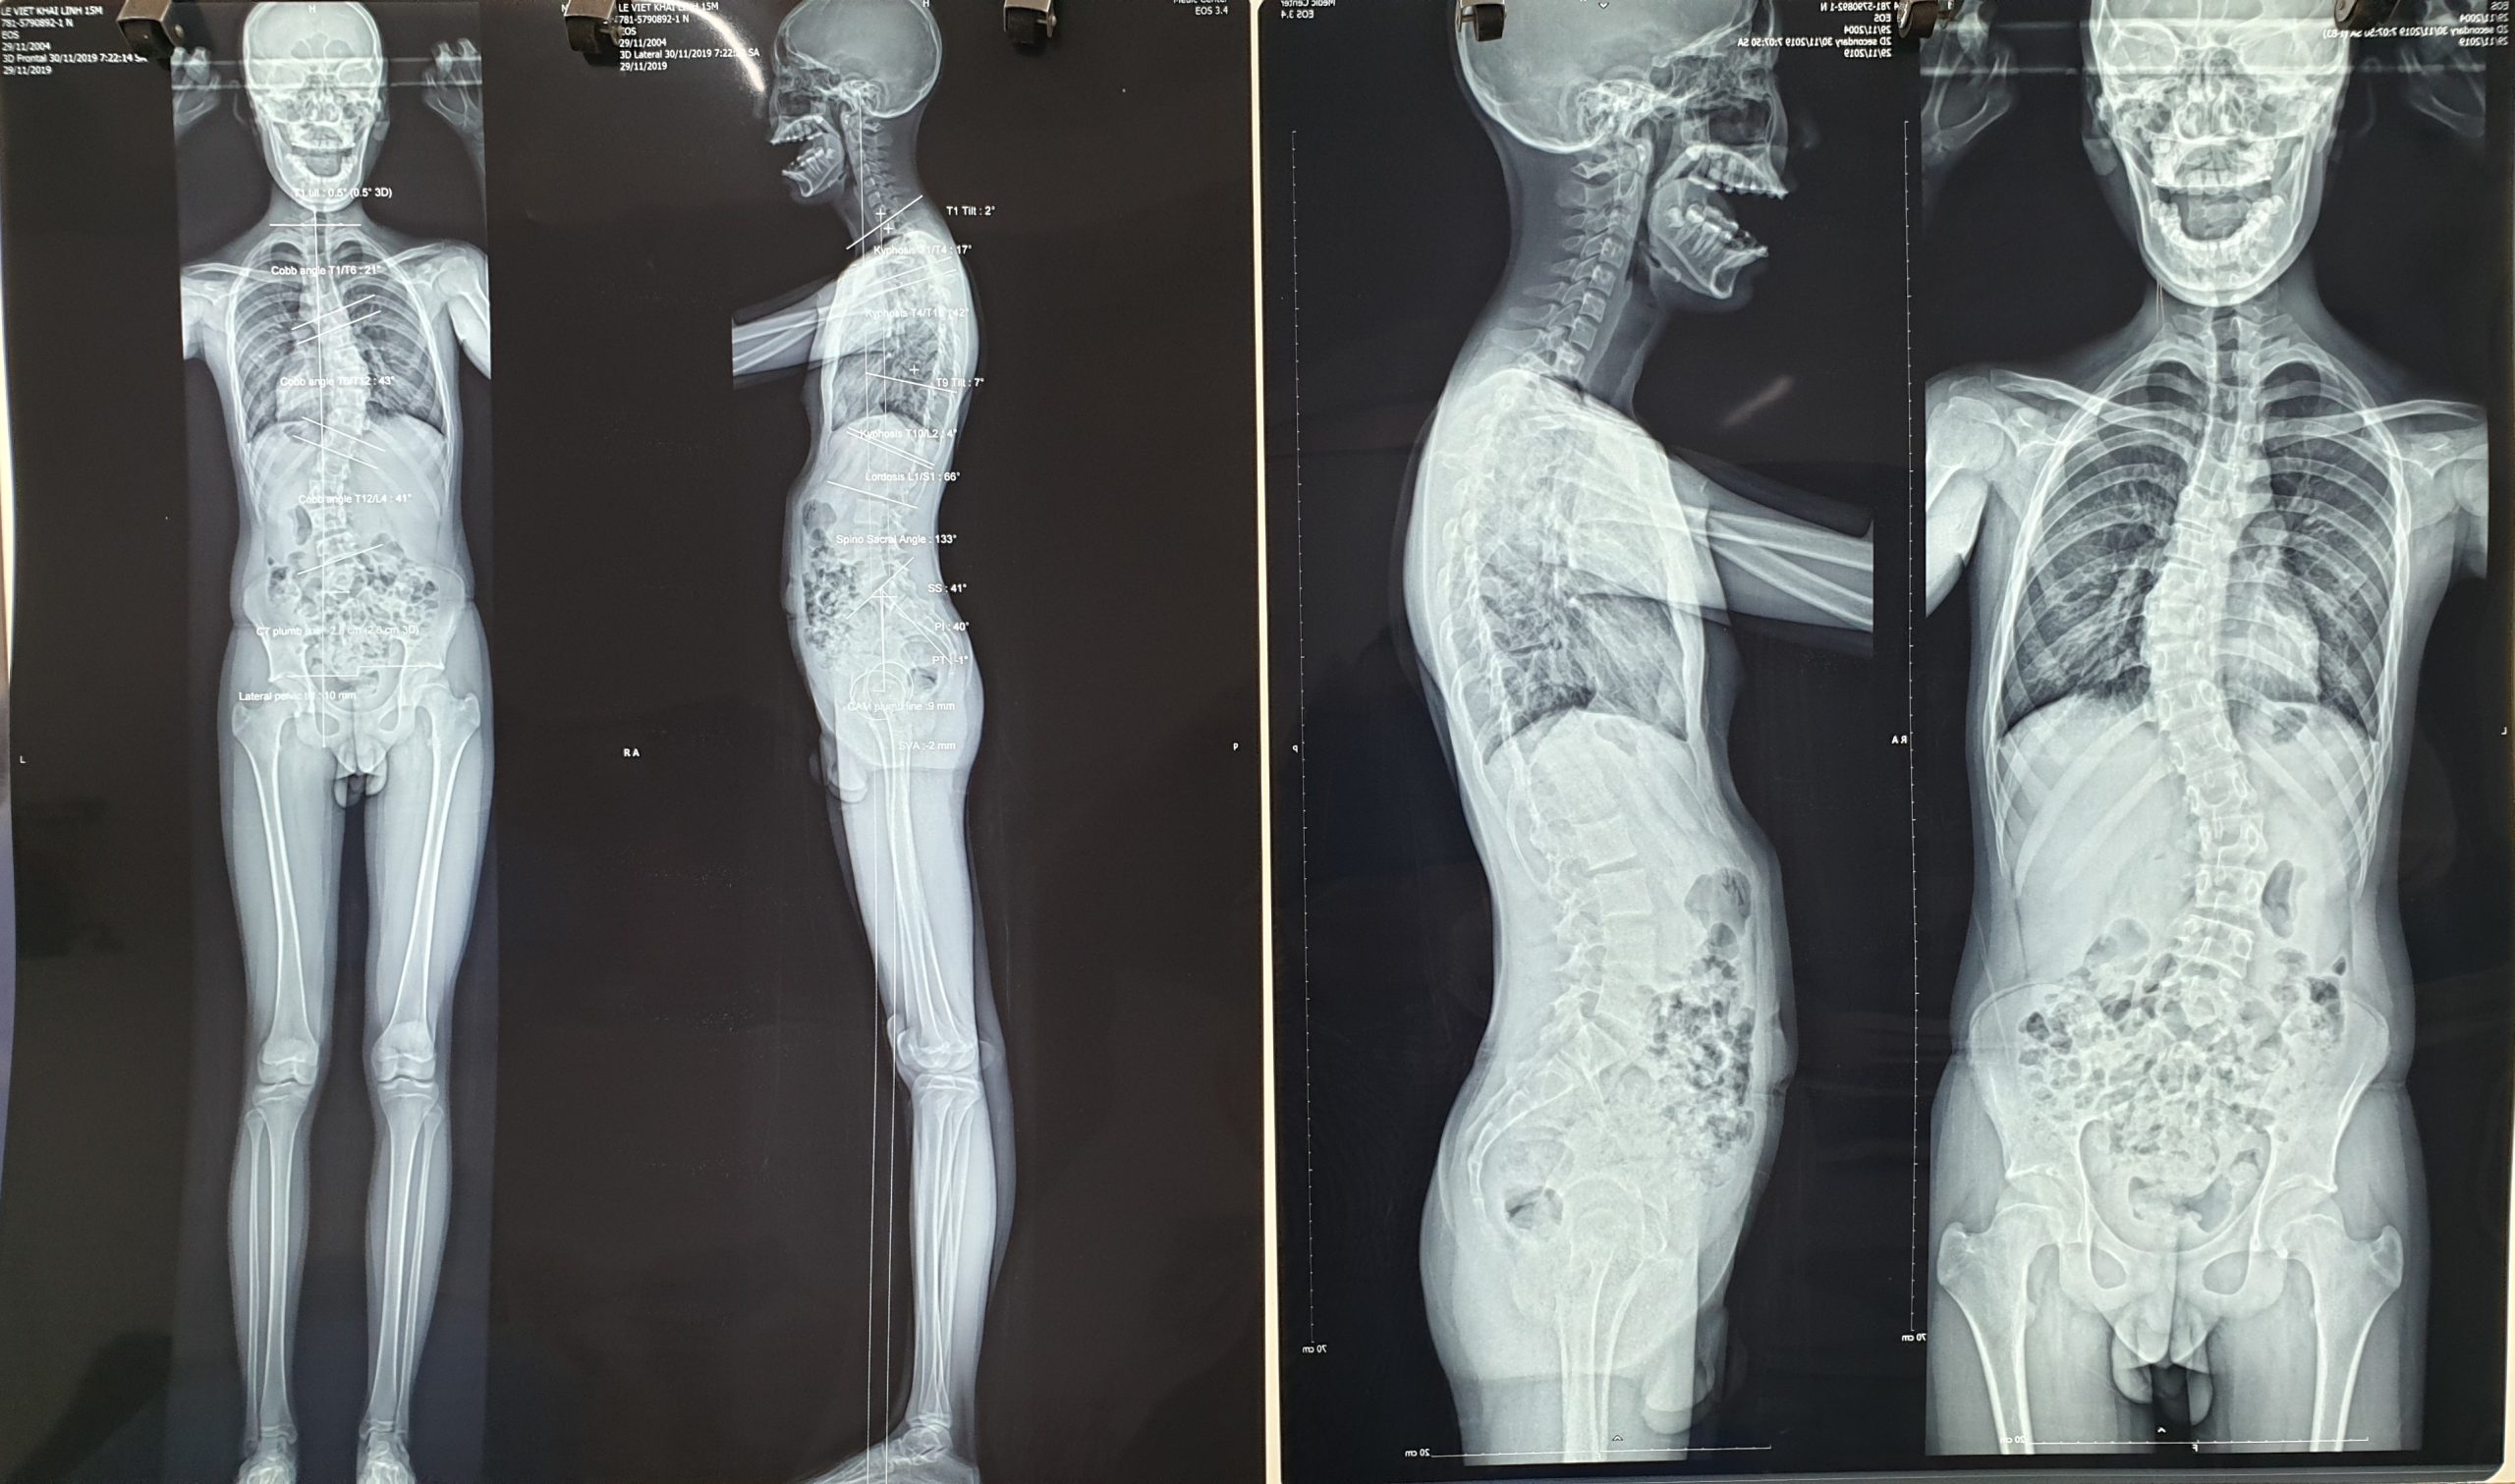

Lê Viết Khải Linh đến từ Đà Lạt – Lâm Đồng; 16 tuổi

Phát hiện cong vẹo cột sống đường cong đôi chữ S: trên 43 độ, dưới 41 độ cobb.

cột sống cong vẹo của khải Linh trước khi điều trị bằng phương pháp áo nẹp chỉnh hình

Con một chàng trai giàu ý chí, nghị lực và quyết tâm cao. Con đã nỗ lực và kiên trì, sau gần 3 năm điều trị bằng phương pháp mặc 2 áo nẹp ngày và đêm. Chạy đua nước rút, bước chân vào đại học cũng là lúc xương con cốt hóa định hình xong.

Con đã làm được, thoát mổ vĩnh viễn, cú lội ngược dòng siêu đỉnh.

Hiện tại con đã 21 tuổi, 3 năm nay học ở nước ngoài nhưng năm nào con cũng về nước ít nhất một lần và lần nào con cũng bay ra bắc để gặp chúng tôi.